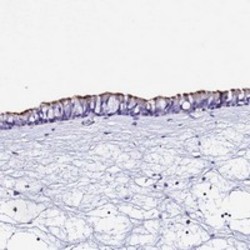

Supportive validation

- Submitted by

- Abnova Corporation (provider)

- Main image

- Experimental details

- Immunohistochemical staining of human nasopharynx with TMEM117 polyclonal antibody (Cat # PAB24485) shows strong membranous positivity in respiratory epithelial cells at 1:200-1:500 dilution.

- Validation comment

- Immunohistochemistry (Formalin/PFA-fixed paraffin-embedded sections)